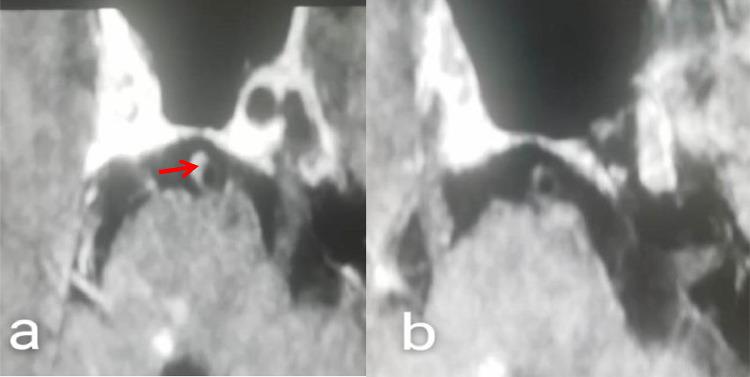

This study used a 3.0T high-resolution magnetic resonance imaging approach to explore basilar artery plaque characteristics in patients suffering from acute isolated pontine infarction.

30 consecutive patients suffering from acute isolated pontine infarction were enrolled in this study and underwent examinations including high-resolution MRI assessment of the basilar artery within 7 days following infarction.

The basilar artery plaque burden of 16 patients with paramedian pontine infarction was 0.26±0.085, while the reconstruction index and enhancement rate index values in these patients were 1.097±0.133 and 1.750±0.447, respectively. In the 14 patients suffering from deep pontine infarction, these three values were 0.21±0.055, 0.896±0.223, and 1.285±0.611, respectively.These values differed significantly when comparing patients suffering from paramedian pontine infarction to those suffering from deep pontine infarction.

This study suggests that the characteristics of basilar artery plaques differ between the two subtypes of pontine infarctions, which may account for the differences in prognosis associated with these two infarct subtypes.